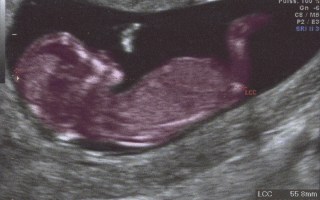

Majority of pregnant women want full genetic profile of their unborn child

Deep genetic screening of fetuses for all Australian mothers could soon be available through a simple blood test – and according to a...